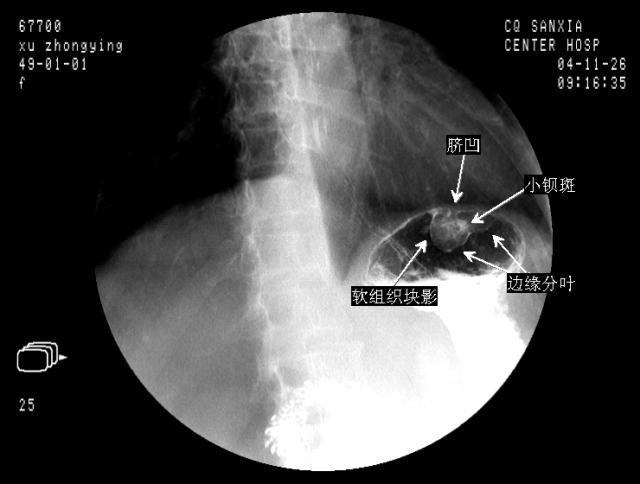

胃底平滑肌瘤

病变基部较宽,边缘光滑,支持胃底良性肿瘤,胃底平滑肌瘤可能!!

单从此片分析:胃底窄基底软组织阴影,病灶上有浓钡点,提示溃疡可能。大小不好测量估计大小2。0厘米。综合考虑为平滑肌肉瘤可能。建议ct了解胃壁情况。